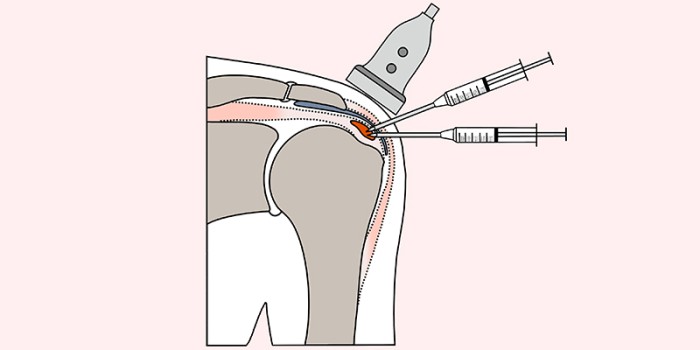

Bij het subacromiale pijnsyndroom (SAPS) betreft het meestal patiënten van 30 tot 60 jaar oud, 2 keer zo vaak vrouwen als mannen.1 De verkalkingen zijn zichtbaar op röntgenfoto’s [figuur 1] of tijdens een echografisch onderzoek, waarbij meestal de supraspinatuspees is aangedaan.234 Het is belangrijk om te beseffen dat rotatorcuffverkalkingen ook aanwezig kunnen zijn bij patiënten zonder klachten (5-10%), maar dat de prevalentie onder patiënten met SAPS-klachten veel hoger is (40-50%).35 Het pathofysiologisch proces is nog niet geheel duidelijk, maar dit kunnen we grofweg indelen in een vaak asymptomatische kalkformerende fase, een rustfase met stabiele klachten en een resorptiefase, waarbij het lichaam de verkalking opruimt. De resorptiefase is niet alleen het pijnlijkste stadium van het ziektebeeld, maar ook de belangrijkste stap in het natuurlijke herstel van de pees.6 Hoewel de klachten dus spontaan kunnen verminderen en de verkalkingen in hun geheel kunnen resorberen, is het beloop zeer wisselend en hebben patiënten soms langdurige en intense klachten.

Figuur 1 | Voor-achterwaartse röntgenfoto van een linkerschouder waarin een verkalking te zien is in het gebied van de supraspinatuspees (links). Alle relevante anatomische structuren (rechts).

Voor-achterwaartse röntgenfoto van een linkerschouder waarin een verkalking te zien is in het gebied van de supraspinatuspees (links). Alle relevante anatomische structuren (rechts).